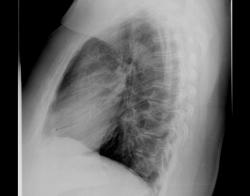

Коллеги, прошу высказать ваше мнение по-поводу отмеченой стрелкой тени. В анамнезе: злокачественная опухоли молочной железы и желудка, выполнена левосторонняя мастэктомия.

Это крупный очаг неоднородной плотности, это очень походит на периферический рак или на очаг Гона. И еще трахея смещена вправо.

похоже на обызвествление реберного хряща.

Посмотрите внимательно, коллеги, а где эта тень на прямой?

Справа от грудной клетки в мягких тканях.

Это не хрящ. Эти тень в проекции 10 сегмента, если смотреть на прямую.

Браво Flaqman! это обызвествленная фиброаденома правой молочной железы

Итак. Татьяна Валентиновна наглядно ответила, что "патологический процесс" в молочной железе может "найти своё отображение" на рентгенограмме органов грудной полости, произведенной в прямой стандартной проекции.

и в боковой тоже...